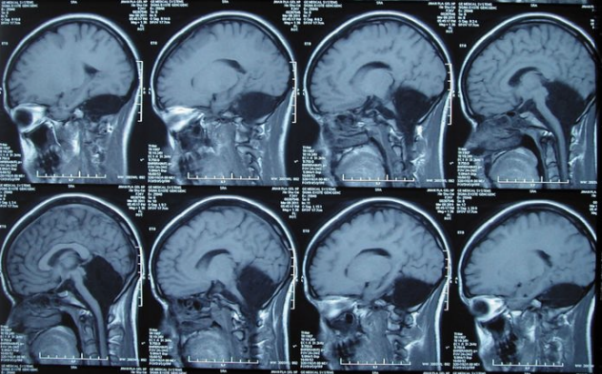

Kiinalaisen naisen aivokuvantaminen ilman pikkuaivoa

Tomografian jälkeen lääkärit tunnistivat välittömästi ongelman lähteen – sen pikkuaivo puuttui. Tila, jossa sen pitäisi olla tyhjä. tämä aivojen alue täytettiin aivo-selkäydinnesteellä, tarjoaa suojaus tautia vastaan. Pikkuaivoissa on noin 10 prosenttia aivojen kokonaistilavuus, mutta sisältää 50 prosenttia neuroneista.

Cerebellar-ongelmat voivat johtaa vakaviin henkisiin ongelmiin taaksepäin, liikuntahäiriöt, epilepsia tai mahdollisesti tappava nesteen kertyminen aivoissa. Kuitenkin klo tälle naiselle pikkuaivojen puute johti vain lievään puutteeseen liikkuminen ja kohtalaiset puheongelmat, kuten lievä ääntäminen.

Lääkärit kuvaavat näitä vaikutuksia “vähemmän kuin voisi olla odottaa “, ja heidän mukaansa hänen tapaus korostaa hämmästyttävää aivojen plastilisuus.